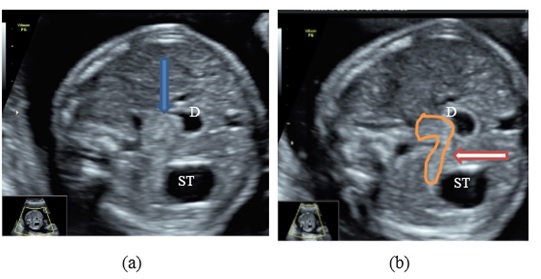

Trong giới hạn của bài này chúng tôi đưa ra dấu hiệu “Rat tail” giúp chẩn đoán tắc tá tràng do màng ngăn là nguyên nhân thường gặp nhất của tắc tá tràng.

Màng ngăn tá tràng là một màng mỏng và trong suốt nên không nhìn thấy được trên siêu âm. Tuy nhiên có thể nhận diện bằng dấu hiệu gián tiếp là “Rat tail”.

Khi có màng ngăn, đoạn ruột trên màng ngăn sẽ bị dãn ứ dịch và đoạn ruột dưới màng ngăn dãn nhẹ và hình ảnh giống như cái đuôi chuột nên được gọi là ‘’rat tail’’ sign.

Trong quá trình siêu âm, khi nghi ngờ là tắc tá tràng do có màng ngăn thì nên kiểm tra cấu trúc tụy để loại trừ nguyên nhân do tụy hình nhẫn.

a. Dấu hiệu ‘’rat tail’’ trên mặt cắt ngang bụng (mũi tên xanh)

b. Hình ảnh tụy bình thường (mũi tên đỏ) trên cùng một bệnh nhân có dấu hiệu ‘’rat tail’’ ST: Dạ dày. D: Tá tràng